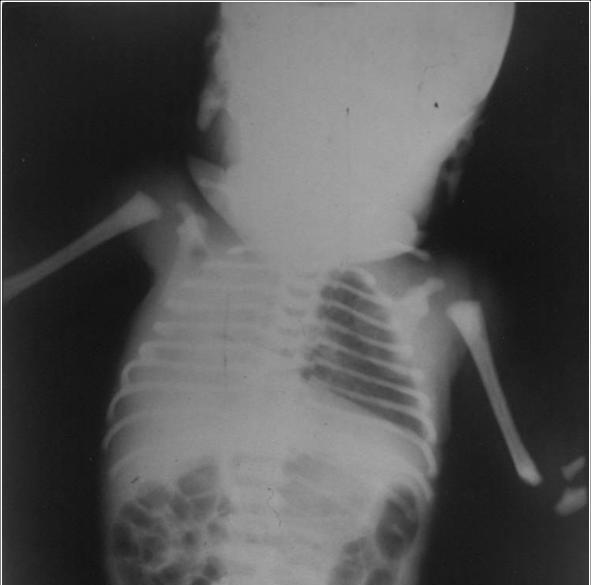

【107-1 醫學(四) 第76題】根據所附影像檢查圖,下列何者為最不可能的診斷?

詳解

破題關鍵

這張嬰兒胸部X光片顯示右側胸腔完全變白,且心臟和氣管都往右邊(病灶側)偏移。這是判斷病因的關鍵。

選項拆解

-A:右肺發育不全(right lung agenesis)會導致右肺體積缺失,造成右側胸腔塌陷,心臟和氣管會被拉向右側。這與影像表現一致。